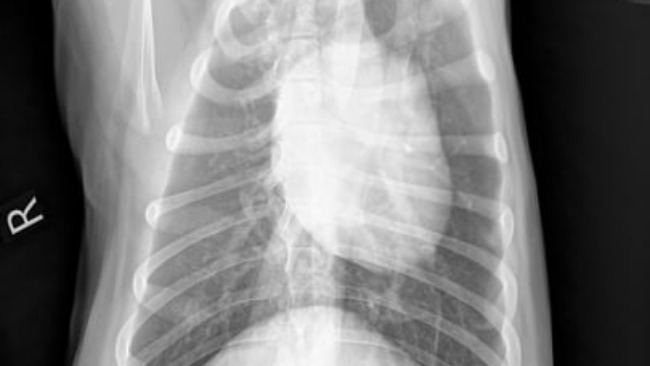

Witam jestem właścicielem suczki o imieniu "Kora". Zbieram pieniądze na operacje dla niej, ponieważ dzisiaj rano (29.01.22) Suczka została potrącona przez samochód i przez to ma problem z kręgosłupem i płucami. Koszt operacji to 4,5 Tysiąca złotych. Piesek ma 3 lata i jest nam bliski, ma jeszcze dużo życia przed sobą... Każda złotówka się liczy. Zdjęcie poniżej. + 1,500 Pobyt w klinice 3 doby.